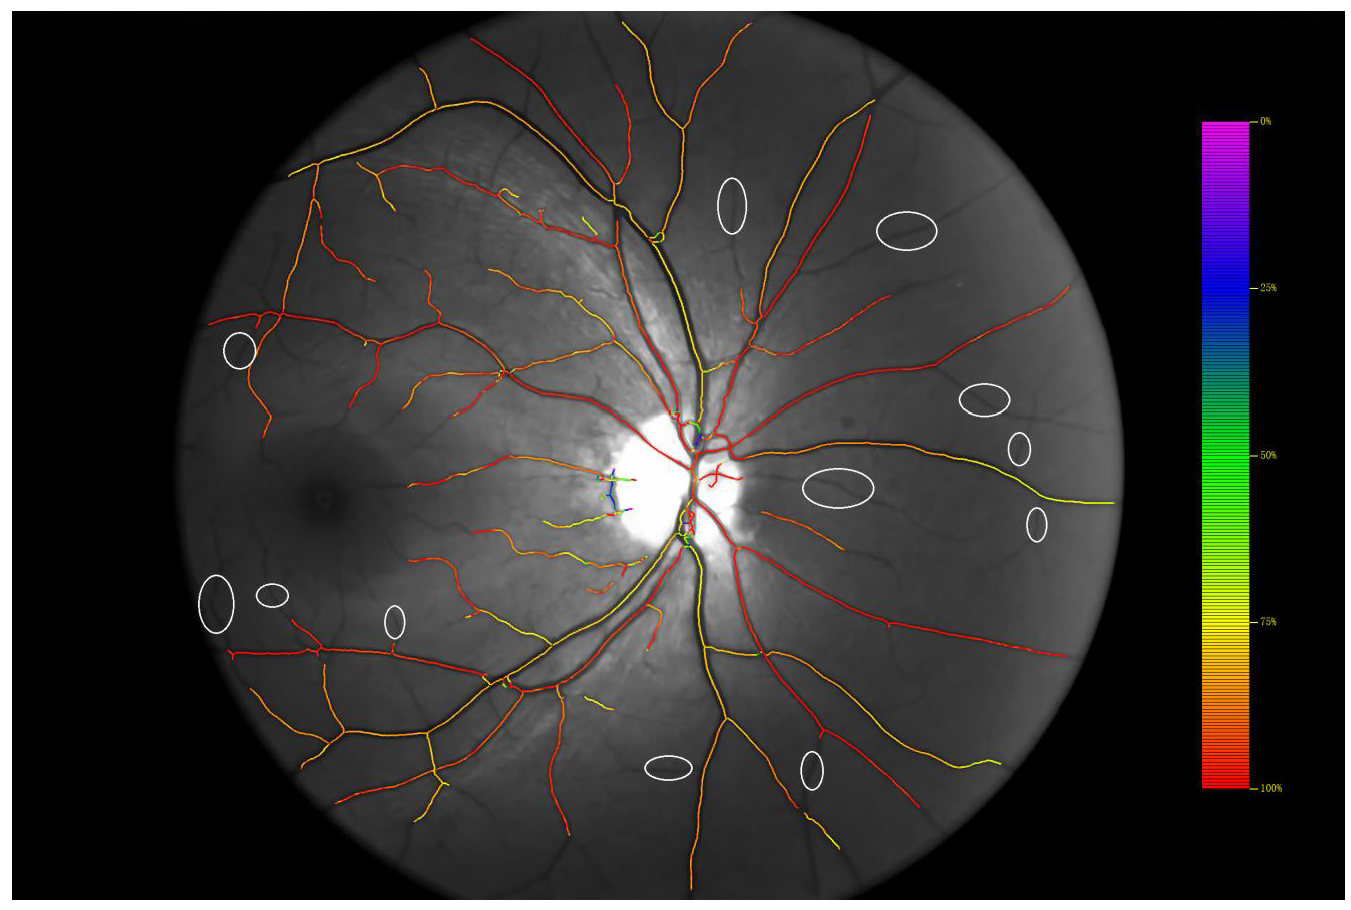

4.1. Comparison of Dual-Wavelength Retinal Image Segmentation Results

4.2. Evaluation of the Effect of the Segmentation Algorithm on the Calculation of SO2